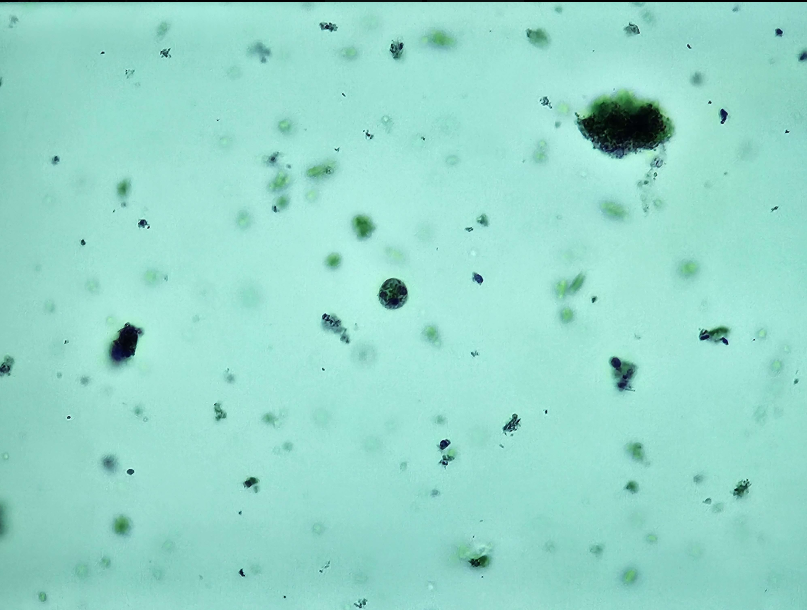

🧠🐌 Acanthamoeba castellani (Trofozoit)

🧩🦠 Organelle:

🔴- pseudopodium (akantopodium);

🔴 - jądro komórkowe + kariosom;

🔴 - wodniczka tętniąca.

😷❓ Parazytoza: Akantomeboza